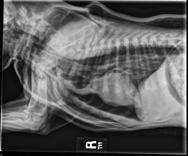

Issuu converts static files into: digital portfolios, online yearbooks, online catalogs, digital photo albums and more. Sign up and create your flipbook.